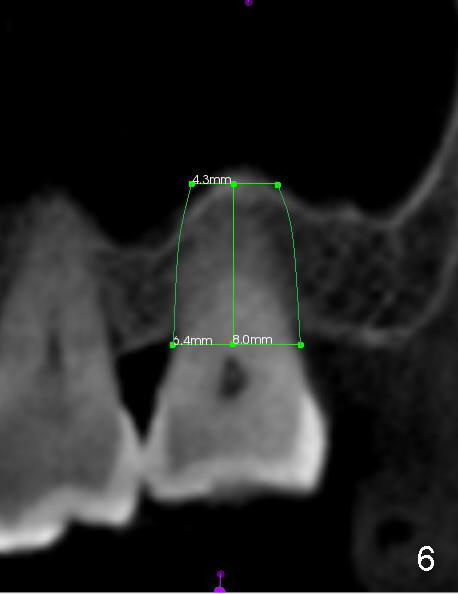

The upper 2nd molar have 3 roots with limited furcation. The buccal ones may be fused (Fig.1 (CT coronal section),2 (sagittal)). After extraction, there are 2 sockets (Fig.1'). When 3 roots are fused, there is a single large socket.

When the buccal roots are fused, there are 3 potential sites for immediate implant (Fig.1'): septum (*), buccal (B) and palatal (P) sockets. Septal placement (6.9x8 mm bone level implant) is the most ideal for restoration (Fig.3). The length of the implant can be increased (10 mm) with sinus lift so that the base of the implant between the buccal and palatal apices in height (Fig.4). Primary stability is derived mainly from the implant body engagement into the septum (Fig.5 coronal section through the septum). If bone density in the septum is high, a small implant may be appropriate (Fig.6,7: 6.4x8 mm). The large implant (6.9 mm) is chosen so that amount of bone graft to be used (Fig.8 red circles) is less.